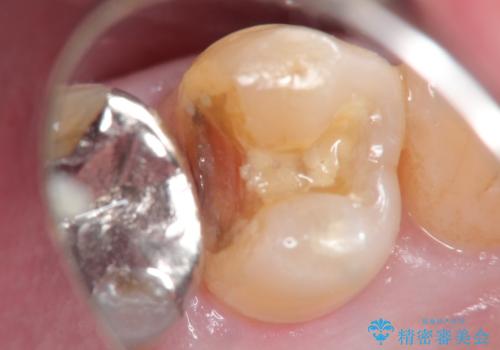

- 銀歯が取れたことを主訴に来院されました。

虫歯も認め、虫歯を除去したのちセラミックインレーにて修復しております。